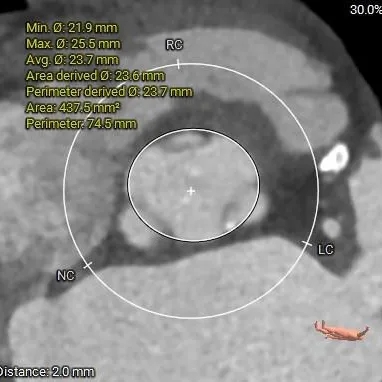

瓣上结构测量

瓣上2mm

23.7mm

瓣上4mm

24.1mm